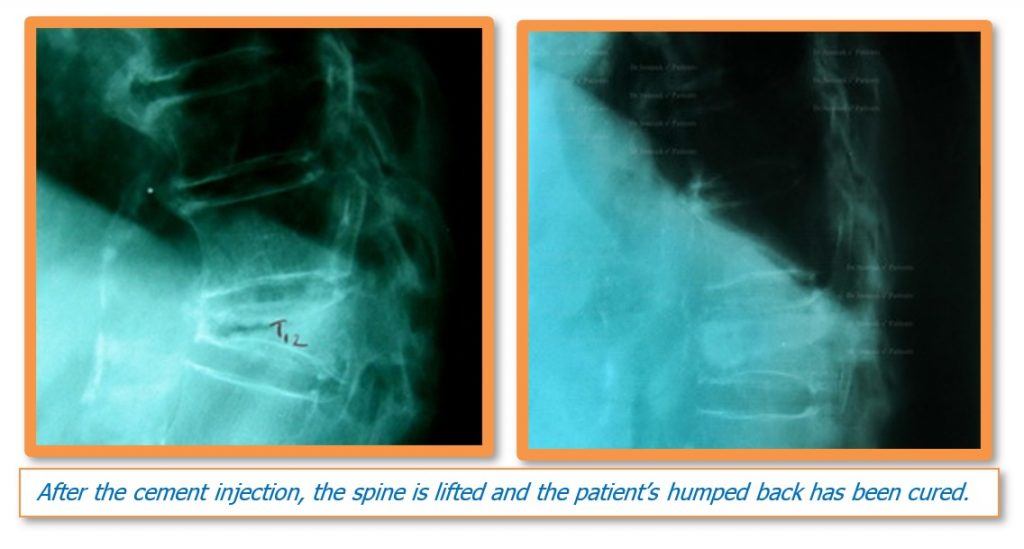

4. Kyphoplasty

Kyphoplasty is when a balloon is placed in the fractured vertebrae. During this process, bone cement is put inside the space made by the balloon. Two long needles are then inserted through the sides of the spinal column into the fractured vertebra body. These needles guide the surgeon while they carefully drill two holes into the vertebral body. There is a large element of skill involved in this process as the needles and drill holes need to be placed in the correct area. The surgeon then slides a hollow tube with a deflated balloon on the end through each drill hole. Inflating the balloons restores the height of the vertebral body and corrects the kyphosis deformity. Before the procedure is complete, the surgeon injects bone cement through a small hole in the skin (percutaneously) into the hollow space formed by the balloon. This fixes the bone in its corrected size and position.

Again, there are advantages and disadvantages of this procedure. One benefit is that no further surgery is required. The procedure also eradicates any severe pain and in fact strengthens the fractured bone. It also gives the advantage of improving some or all of the lost height in the vertebral body. Additionally, the patient will usually recover very quickly; in some cases patients have been known to get up to perform routine activities only a day after the surgery. Furthermore, patients will not need to stay in bed, even during cases, as mentioned previously, when they constantly have to lie down due to the amount of pain caused by body movements. Other advantages are that there will not be a large surgery wound, as well as minimal blood loss for the patient.